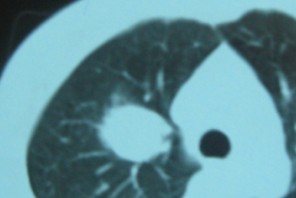

标题: CT192450:男37,自觉胸闷两月余 [打印本页]

标题: CT192450:男37,自觉胸闷两月余

右肺上叶良性肿瘤---错构瘤/硬化性血管瘤/炎性假瘤等。

考虑血管源性肿瘤,硬化性血管瘤可能性大;

不除外错构瘤。

边缘有毛刺,考虑癌

硬化性血管瘤  可能性大,建议增强